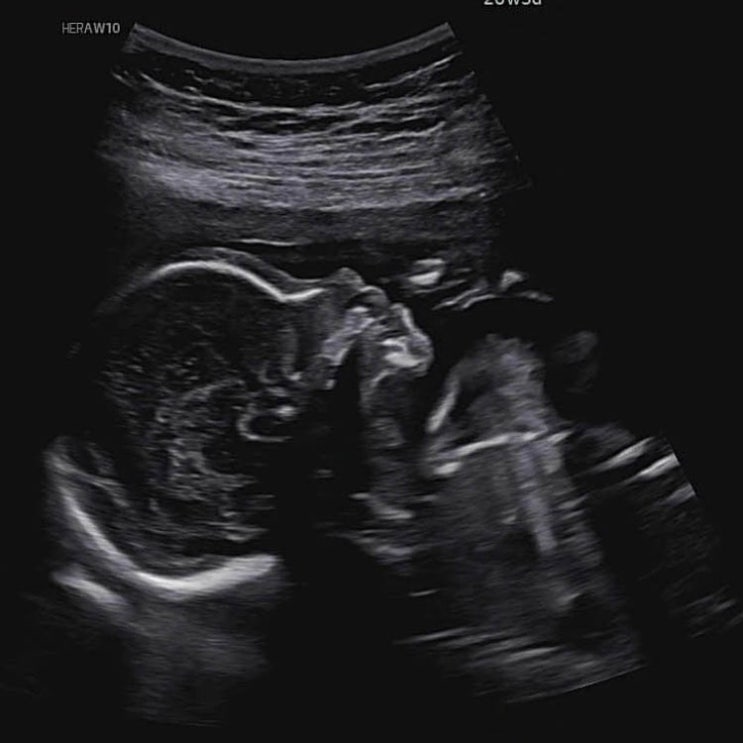

[임신 20주차] 정밀검사, 역아 / 강원도여행

임신 20주차 증상? 가슴에 무언가 가득차고 쥐어짜는 느낌 배가 많이 나온다. 체중이 증가한다. 20주는 ...